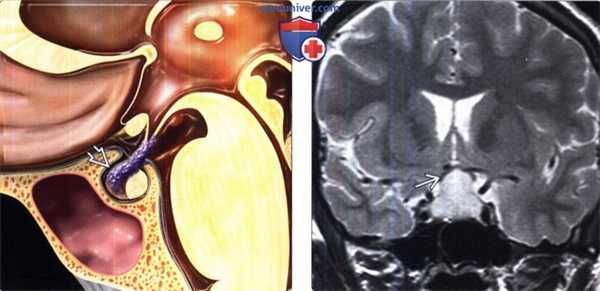

(Слева) На рисунке сагиттального среза показан лимфоцитарный гипофизит. Обратите внимание на утолщение воронки с исчезновением нормального ее сужения «сверху вниз», а также инфильтрацию передней доли гипофиза.

(Справа) МРТ, Т2-ВИ, корональный срез: у беременной женщина со зрительными и эндокринными нарушениями в селлярной/супраселлярной областях определяется гиперинтенсивное объемное образование, смещающее зрительный перекрест кверху. При хирургическом вмешательстве с целью декомпрессии зрительного перекреста был выявлен лимфоцитарный гипофизит Рентгенологическая картина имитирует макроаденому гипофиза.

(Слева) МРТ, постконтрастное Т1-ВИ, сагиттальный срез: у мужчины 37 лет с пангипопитутаризмом на фоне лечения ипилимумабом по поводу метастатической меланомы отмечаются относительно крупные размеры гипофиза. По сравнению с предыдущей МРТ, проведенной шесть недель назад, размеры железы увеличились вдвое. Такая картина согласуется с лекарственно-индуцированным гипофизитом.

(Справа) МРТ, постконтрастное Т1-ВИ, сагиттальный срез: у пациента в возрасте 50 лет с несахарным диабетом определяется локальное утолщение воронки гипофиза, обусловленное лимфоцитарным инфундибулонейрогипофизитом.